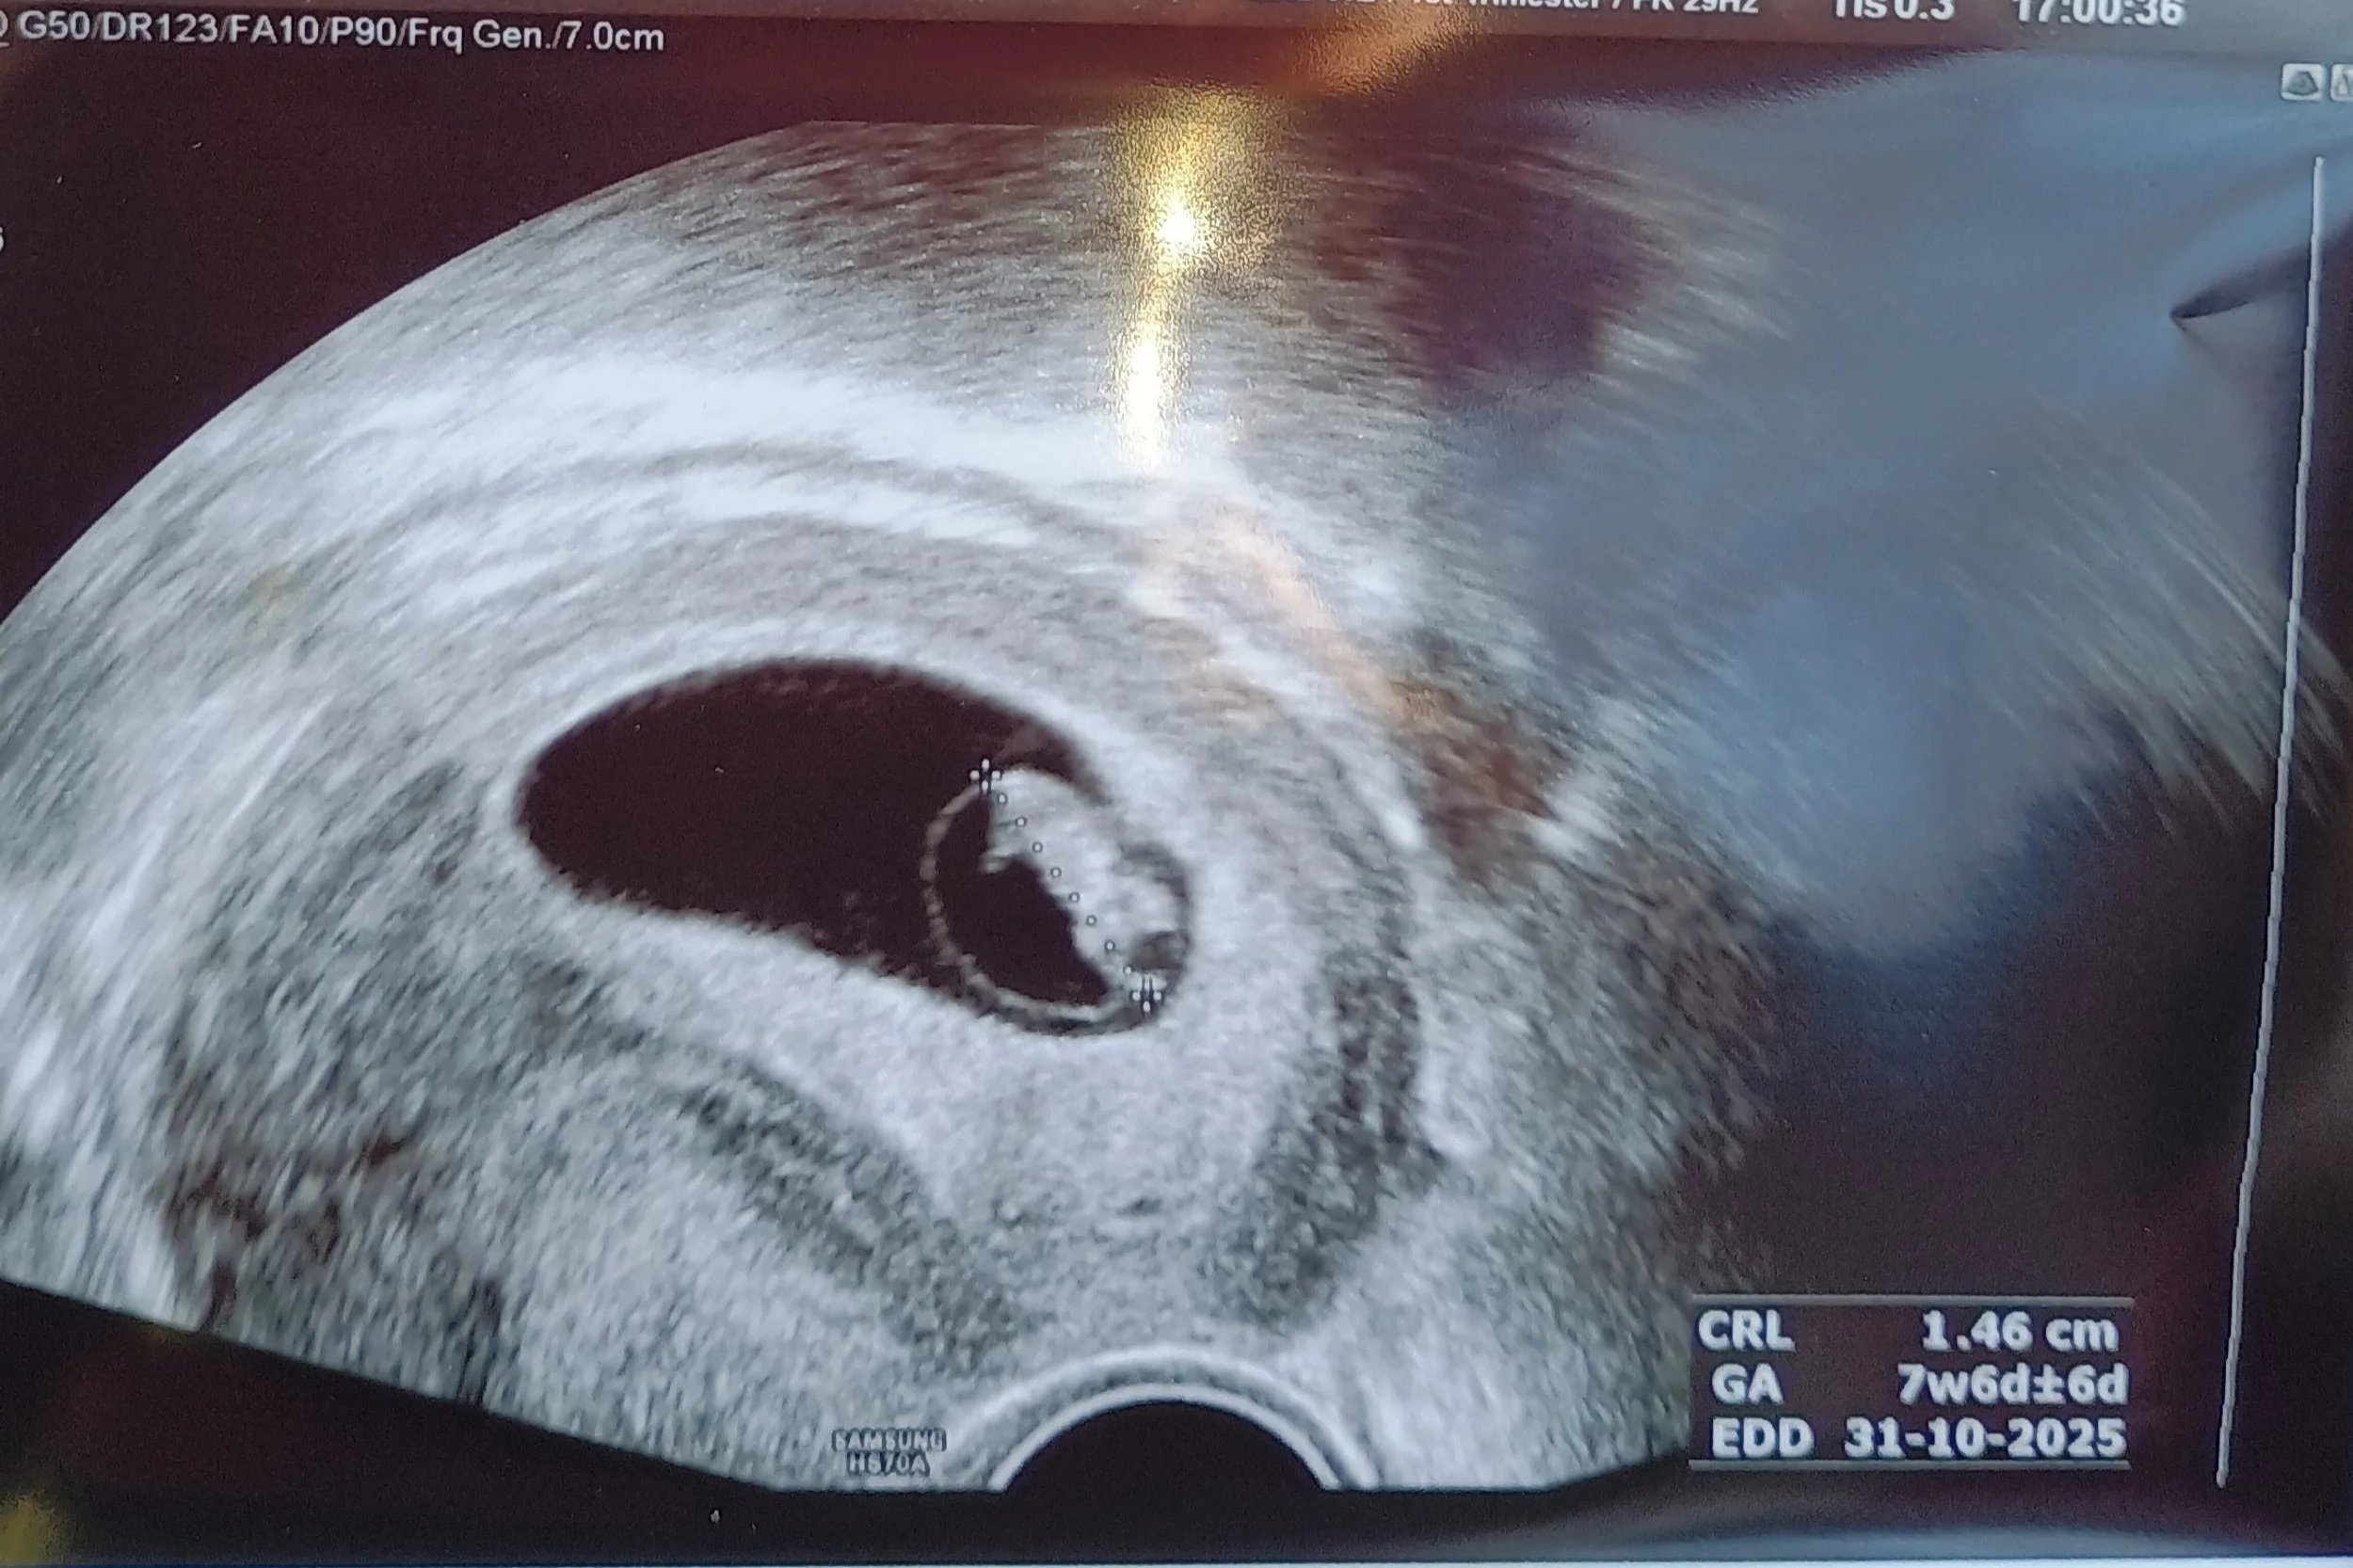

Mijn eerste trimester – een rollercoaster met diabetes

Mijn tweede trimester met type 1 diabetes